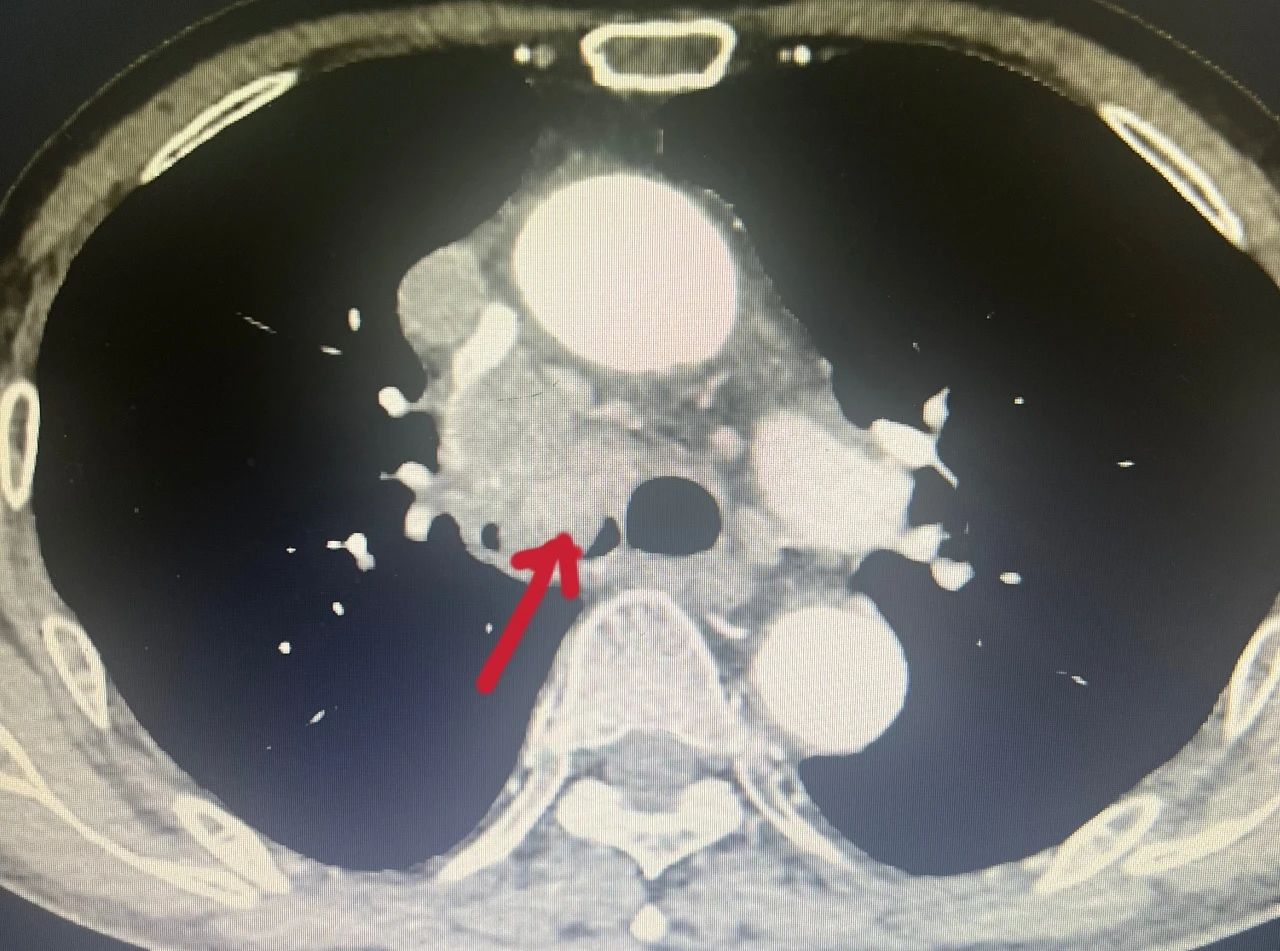

“支气管肿瘤”对人们来说比较陌生,它是呼吸系统的少见病症,以往的常规治疗手段是手术切除肿瘤后进行气管重建,手术难度大、风险高。为了减轻支气管肿瘤患者的身体负担,景德镇市第一人民医院呼吸与危重症医学科积极推动技术创新,成功引进并成熟开展多例经支气管镜高频电圈套切除术,为多名支气管肿瘤患者顺利“拆弹”,使患者们恢复畅快呼吸。 CT显示右侧气管内有巨大肿瘤 李大爷今年71岁,六个月前确诊为肺肉瘤样癌,一个月前间断性咳血,呼吸困难,最近感觉情况加重,到景德镇市第一人民医院呼吸与危重症医学科就诊。11月30日,患者出现意识模糊、血气提示急性呼吸衰竭。 “呼吸的通道堵塞严重,情况很危险,随时都可能窒息。”市一院呼吸与危重症医学科主任卢志军介绍。通过综合评估患者年龄、耐受能力、影像学特征,呼吸与危重症医学科团队最终决定对患者实施支气管镜高频电圈套器肿瘤切除术。“这样可以切除病灶,迅速解除气道阻塞,缓解症状”。 卢志军正在进行支气管镜手术(资料图片) 术前工作准备就绪,手术紧张有序的进行。随着气管镜进入患者的主气管时,看到患者右侧主气管内一个圆形“硕大”的肿瘤,卢志军通过电圈套器对肿瘤进行套扎,同时使用氩气刀辅助切割和止血,肿瘤顺利切除,随后采取冷冻处理减少肉芽和肿瘤组织生长,最后使用电凝术对肿瘤根部进行最后的处理和止血,手术用时仅15分钟,最终气道顺利再通,末梢血氧也由术前的60%升至正常。李大爷现已顺利出院。 术前术后对比图 经支气管镜高频电圈套切除术是呼吸内镜下支气管肿物切除术常用手段之一,通过纤支镜检查可以在镜下直视气管、支气管的粘膜是否发生病变、管腔是否通畅,通过对病变部位进行组织活检、刷检以及肺泡灌洗可协助疾病诊断。此外,通过支气管镜还可以进行较多的镜下治疗,高频电圈套就是其中一种。该项技术利用高频电圈套将气管内的新生物套住,自新生物根部将其切除,高频电圈套的优点是可以切除较大块的肿物,并且出血少、安全性高、患者花费低、操作时间短,甚至仅使用局部麻醉就可以完成,与全身麻醉相比,并发症少,安全性更高。对于气管、支气管的气管息肉、良性肿瘤、平滑肌瘤及恶性肿瘤的姑息治疗,有较好的治疗效果。 呼吸与危重症医学科简介 景德镇市第一人民医院呼吸与危重症医学科成立于2010年10月,经过不断发展壮大,现已形成具有规模和专科医疗特色的医教研全面发展的科室,2020年与江西省胸科医院为省市共建学科。 科室开放普通床位 98 张,重症监护床位 6 张。配有医师 19人,护士 64人,其中医师高级职称 6人,主治医师 9人,住院医师 4 人,副主任护士4人,主管护师 4人等,其中硕士 5 人。 除了呼吸科常见病、慢性阻塞性肺病、各种呼吸衰竭及间质性肺病、肺结节病及肺心病等呼吸危重症疾病的诊治,近年来,科室不断开展了肺癌的早期诊断及个性化治疗,支气管镜检查、内科胸腔镜检查及各种介入治疗,及置入细管胸腔闭式引流术治疗气胸及胸腔积液, 经彩超或 CT 引导经皮肺穿刺活检技术,经支气管镜肺活检,肺段灌洗,钳取异物,经支气管镜引导气管插管术,经支气管镜氩气刀治疗技术、冷冻治疗技术,球囊扩张,支架植入治疗恶性肿瘤大气道狭窄,内科胸腔镜诊疗技术,经皮穿刺置入 125I 粒子治疗肺恶性肿瘤技术,床旁支气管镜检查等各种急危重症救治技术等。还有已购入超声支气管镜和硬质支气管镜,即将开展超声支气管镜检查及淋巴结穿刺活检术,硬质支气管镜技术等。